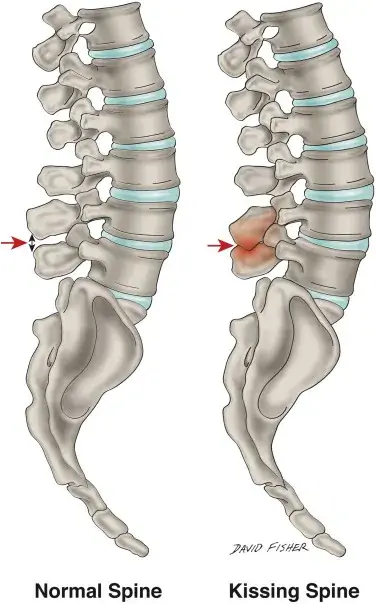

Kissing Spine (Baastrup Syndrome) - Infographic - Mississauga Osteopathy Clinic

Baastrup Syndrome, also called kissing spine, involves contact between adjacent spinous processes in the spine. This condition was first described in 1933. It most often affects the lumbar spine and rarely the cervical spine.

When two neighboring spinous processes touch during movement, mechanical irritation develops. This contact leads to localized back pain. The condition is often misdiagnosed because symptoms resemble other spinal disorders.

kissing spine